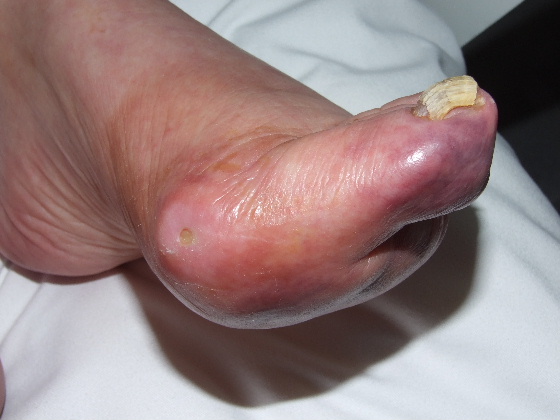

Podagra gotosa. Hiperqueratosis.